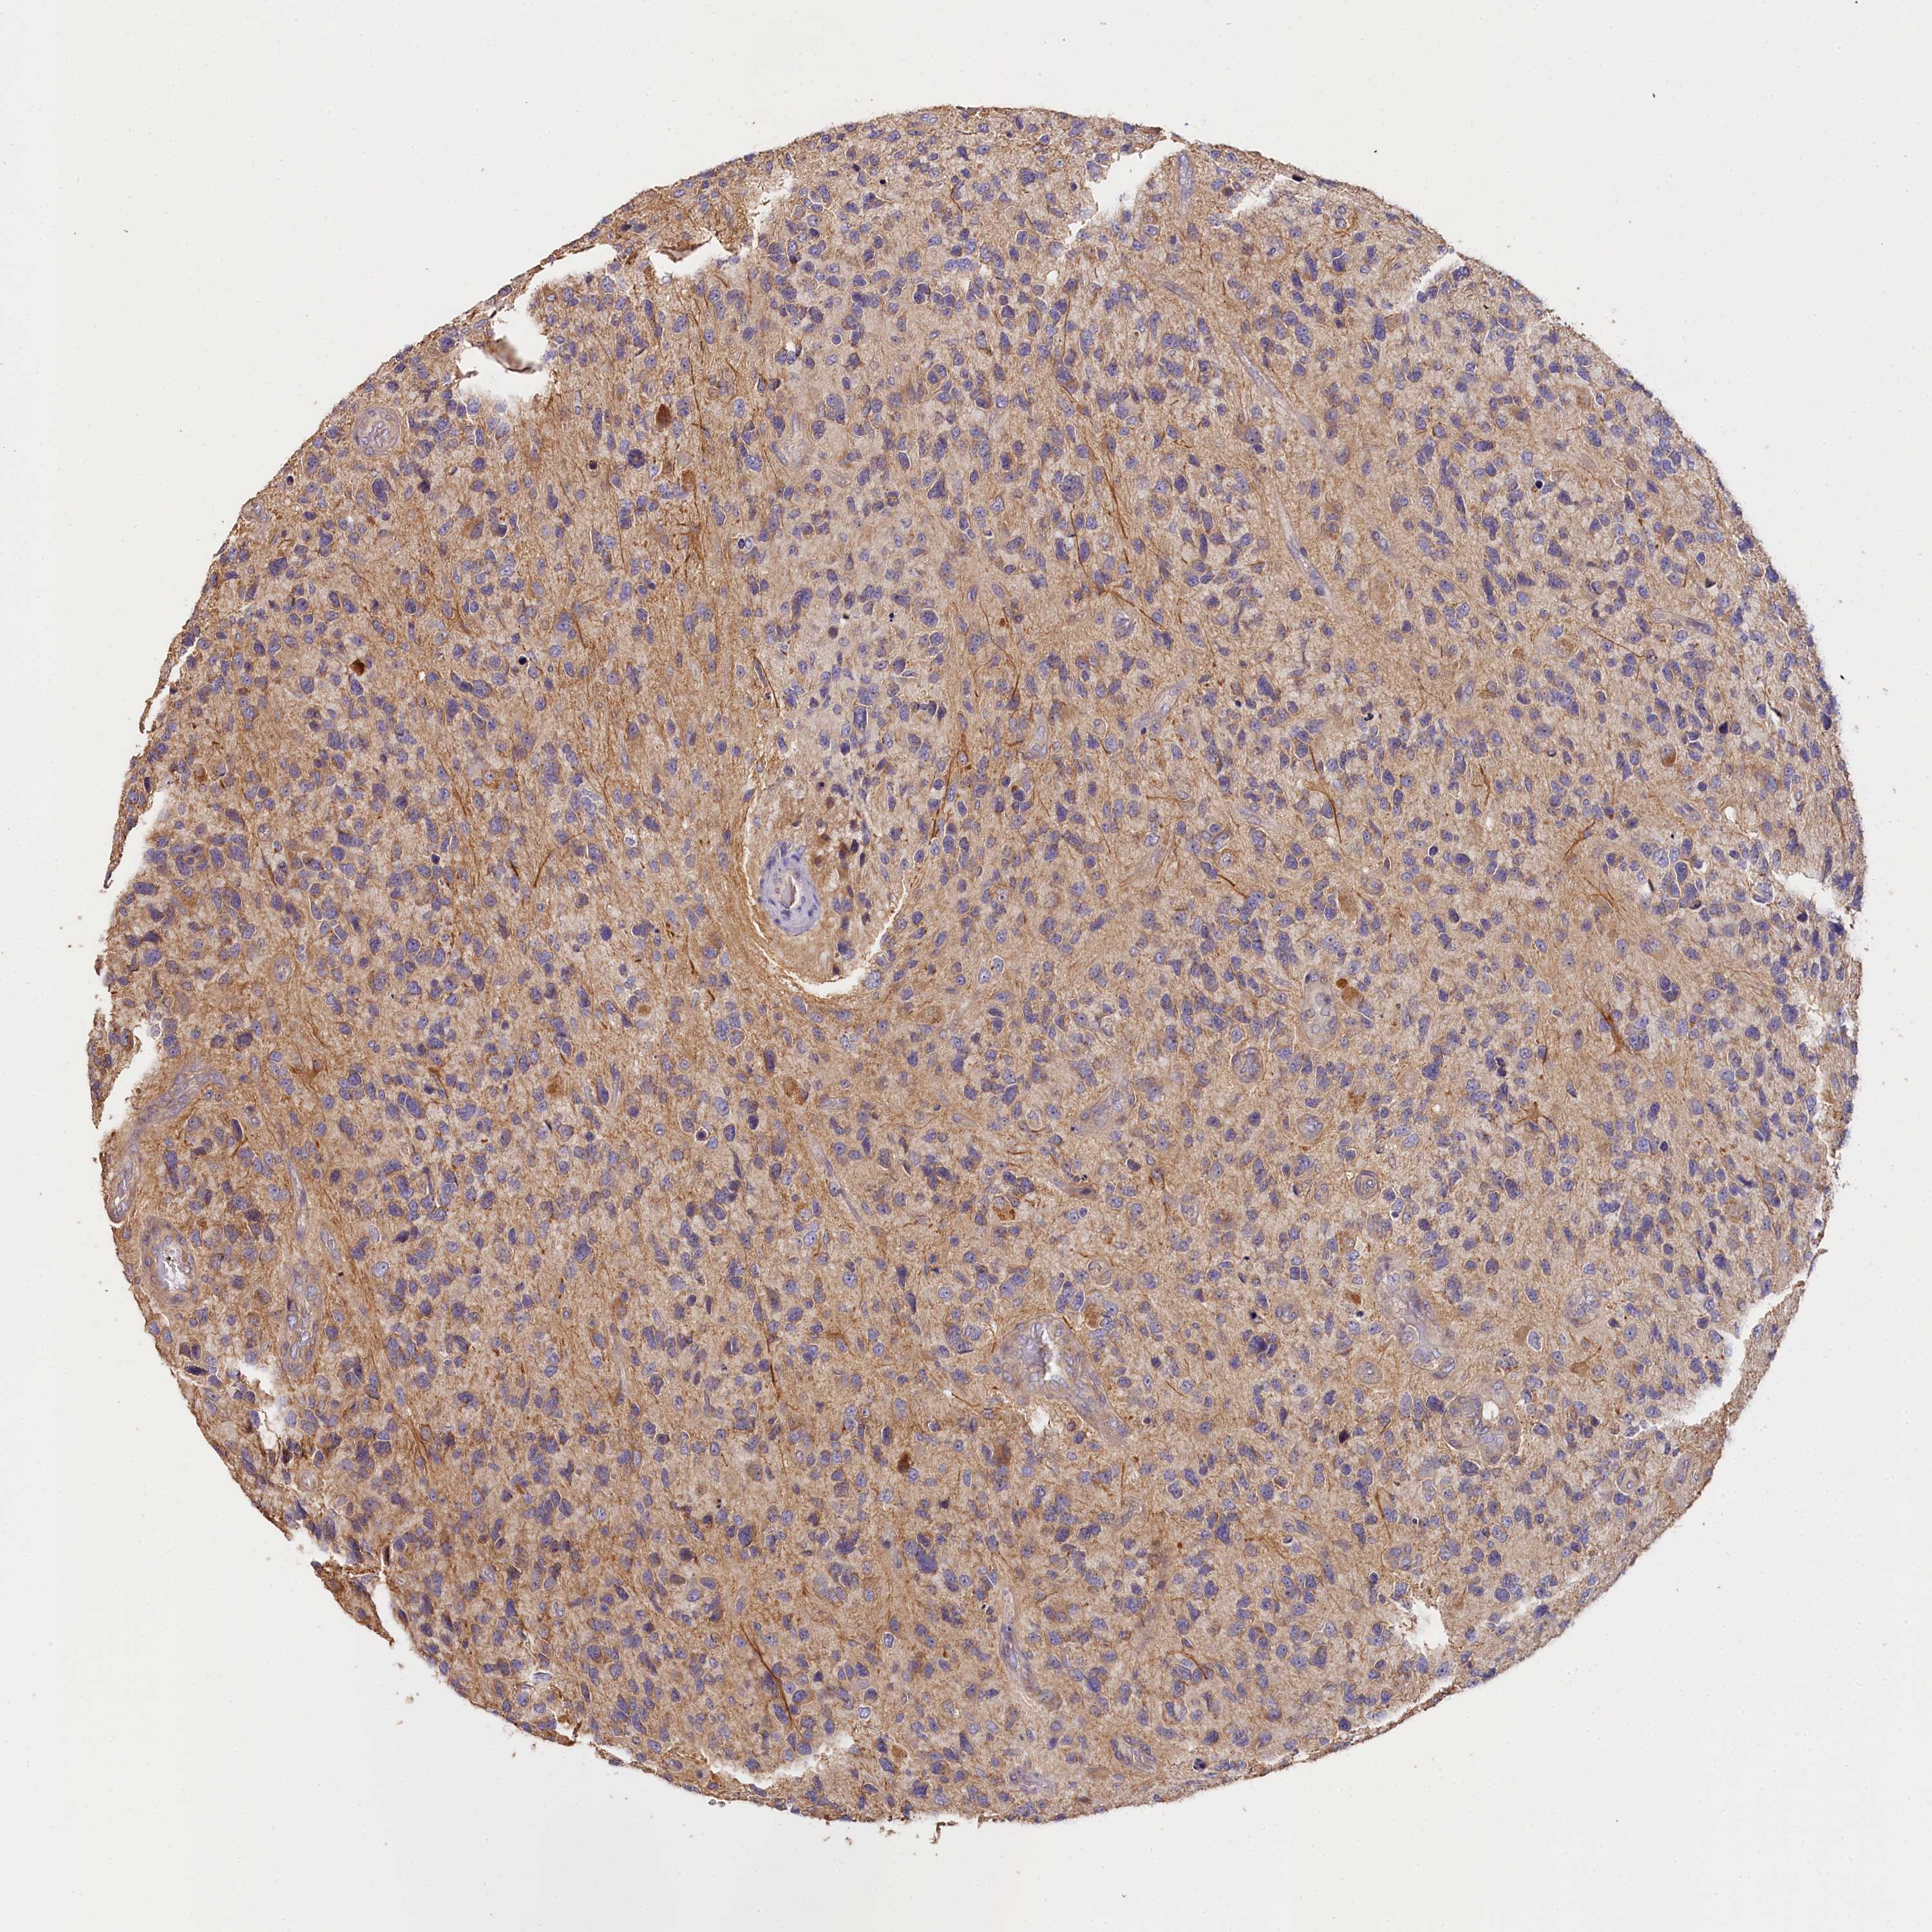

GLIOMA - Protein expressioni

A mouse-over function shows sample information and annotation data. Click on an image to view it in a full screen mode. Samples can be filtered based on level of antibody staining by selecting one or several of the following categories: high, medium, low and not detected. The assay and annotation is described here.

Note that samples used for immunohistochemistry by the Human Protein Atlas do not correspond to samples in the TCGA dataset.

Antibody stainingi

Antibody staining in the annotated cell types in the current human tissue is reported as not detected, low, medium, or high, based on conventional immunohistochemistry profiling in selected tissues. This score is based on the combination of the staining intensity and fraction of stained cells.

Each image is clickable and will lead to virtual microscopy that enables deeper exploration of all samples and also displays staining intensity scores, fraction scores and subcellular localization as well as patient and tissue information for each sample.

Antibody HPA041165

Antibody HPA041839

Staining

High

Medium

Low

Not detected

Intensity

Strong

Moderate

Weak

Negative

Quantity

>75%

75%-25%

<25%

None

Location

Nuclear

Cytoplasmic/membranous

Cytoplasmic/membranous,nuclear

Glioma, malignant, High grade

Glioma, malignant, Low grade